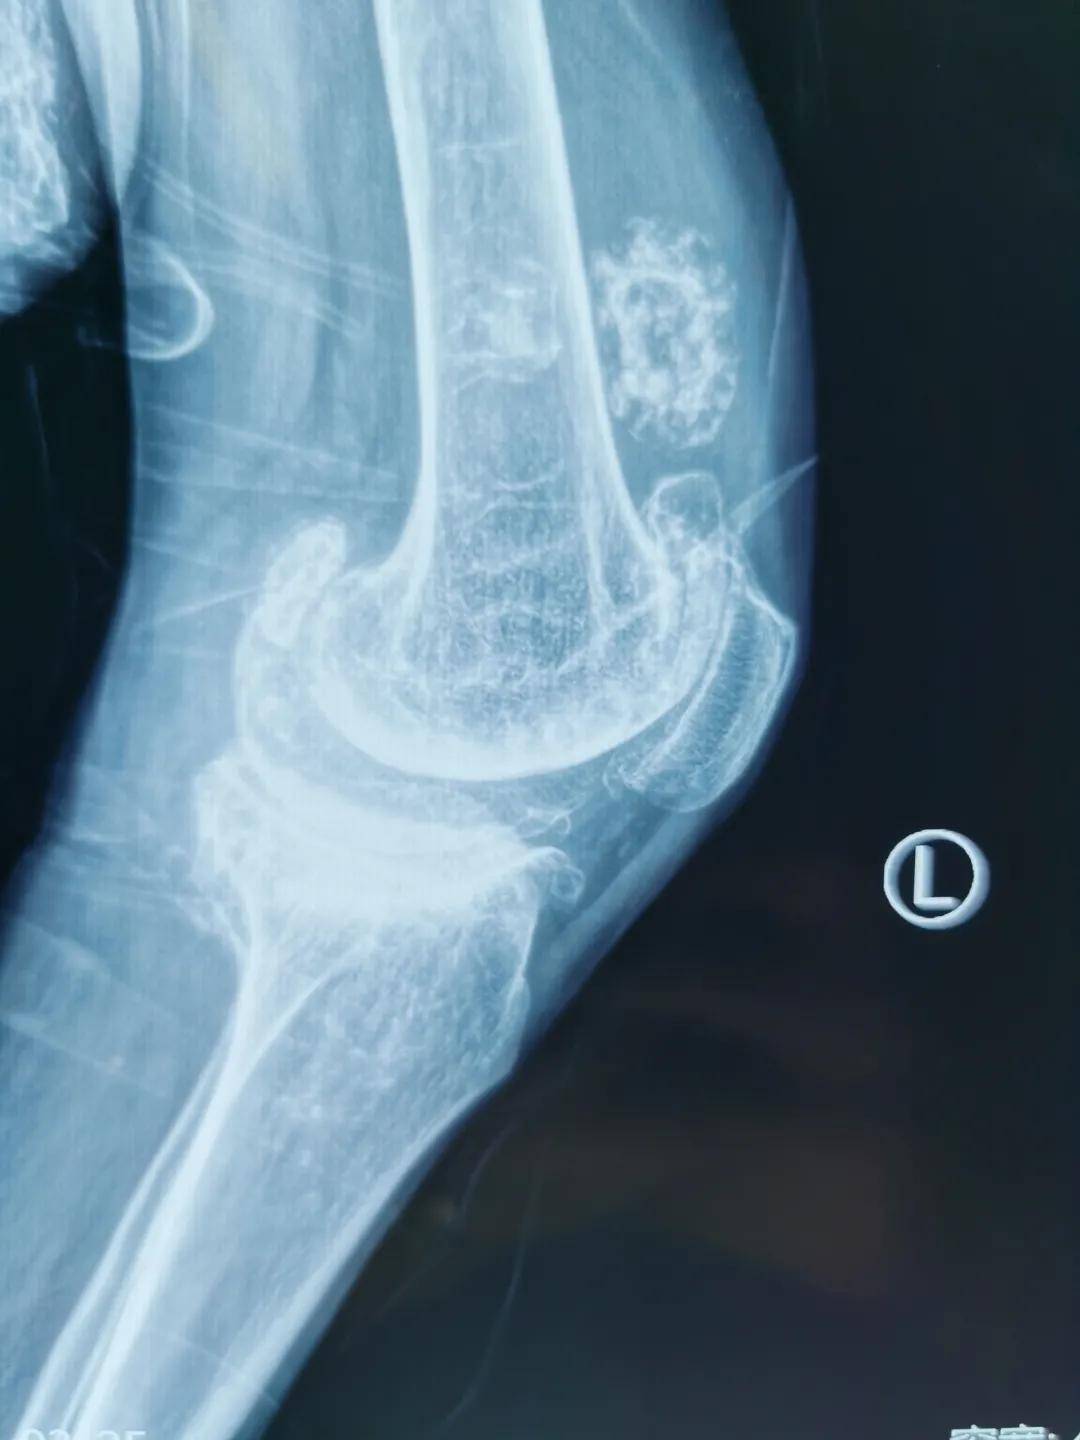

完善各项相关检查后 , 在郭浩院长带领下 , 邀请麻醉科、器械厂家、护士进行学科讨论 , 制定了精细的手术方案 , 由于患者双膝外翻畸形大于30度 , 术前因疼痛完全丧失独立行走能力 , 膝关节外翻畸形的膝关节置换难度大 , 外侧软组织松解困难 , 易出现髌骨脱位 , 神经损伤等并发症 。 在充分完成各项准备后 , 于2021年4月在全麻下行“右侧人工全膝关节置换术” , 术中生命体征平稳 , 手术历时2小时 , 顺利结束 , 患者恢复良好 , 术后第三天便在助步器保护下下地活动 。

此例手术为患者实现了十余年不能站立的行走梦 , 患者看到自己笔直的双腿 , 激动的掉下眼泪 。 西安市红会医院阎良院区在总院的支持与帮助下 , 骨科已经完成了许多例高难度手术 , 优质资源下沉到基层 , 以三级医院的诊疗水平 , 为富阎板块以及周边许多地区患者解决了看病难、就医难问题 , 得到了周边老百姓的信赖与赞扬 。